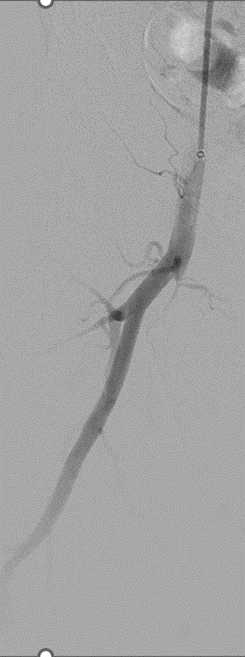

★ Case 6

Severecalcification

左右滑动查看